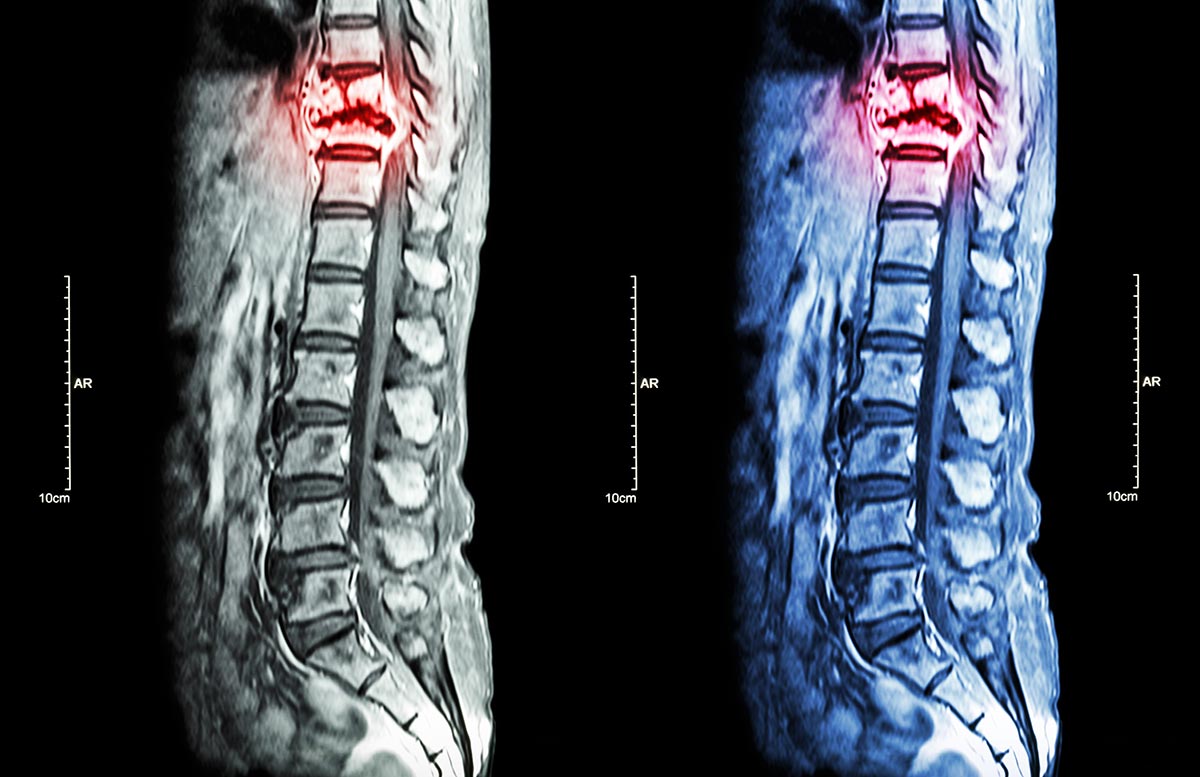

Bei einem Bandscheibenvorfall (Diskusprolaps) kommt es zu einem Austritt oder einer Vorwölbung von Bandscheibengewebe, wodurch benachbarte Nervenwurzeln oder – im Bereich der Hals- und Brustwirbelsäule – auch das Rückenmark beeinträchtigt werden können. Bandscheibenvorfälle können an der Hals-, Brust- oder Lendenwirbelsäule auftreten und führen je nach Lokalisation zu unterschiedlichen Beschwerdebildern.

An der Lendenwirbelsäule äußert sich ein Bandscheibenvorfall häufig durch Rückenschmerzen mit Ausstrahlung in ein oder beide Beine, begleitet von Kribbeln, Taubheitsgefühlen oder Kraftminderung. An der Halswirbelsäule stehen Nackenschmerzen mit Ausstrahlung in Schulter, Arm oder Hand im Vordergrund, häufig verbunden mit Sensibilitäts- oder Feinmotorikstörungen. Bandscheibenvorfälle der Brustwirbelsäule sind seltener und können sich durch gürtelförmige Schmerzen, Missempfindungen im Rumpfbereich oder – in ausgeprägten Fällen – durch neurologische Ausfälle äußern.

Bei anhaltenden Beschwerden, zunehmenden neurologischen Ausfällen oder relevanter Nerven- bzw. Rückenmarkskompression sind operative Maßnahmen indiziert. Diese erfolgen in der Regel in minimalinvasiver mikrochirurgischer Technik, in ausgewählten Fällen auch endoskopisch. Ziel der operativen Behandlung ist die Entlastung der betroffenen Nervenstrukturen bei möglichst gewebeschonendem Vorgehen.